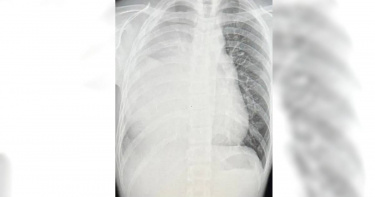

21歲男子不抽菸,喜歡喜歡從事爬山、騎腳踏車等戶外運動,結果今年7月因胸痛就醫後,透過X光照發現他的肺部已經白了一片,後續再做電腦斷層、核磁共振等檢查,竟確診「生殖細胞瘤」,只見縱隔腔長了15公分大的腫瘤。原PO透露,化療期間醫生的一句話也讓他忍不住邊聽邊哭「我才21歲耶。」一名男網友近日在Dcard以「21歲的我只剩下一個肺」為題發文指出,「我本身沒有抽菸,但是我家人有很多都有抽菸,不知道是不是有影響到?!」他表示今年7月8日他突然胸痛,就醫照X光後驚見「肺部白了一片」,醫師馬上幫他轉診到林口長庚胸腔內科,隨即開始就一連串的檢查,「照了一堆電腦斷層、核磁共振後,發現我的縱隔腔長了15公分大的腫瘤,馬上安排了切片。」原PO表示,7月底「第一次化療,此時腫瘤已經長到20公分了」他感嘆,「化療後超想吐、噁心、食慾不振、做惡夢,真的好痛苦,每天每天心情都好差」,做完3次化療後,「腫瘤持平沒有變大縮小,但是在壞死的過程中腫瘤纖維化了」,更讓他痛心的是,「醫生告訴我我一輩子只剩下一邊的肺了,一邊已經失去功能了,聽完的當下我馬上就哭了,我心想我才21歲耶。」他無奈表示,「我不知道以後的日子會是怎樣,會不會有一天復發我就死了,一切的未知不安在我腦海裡迴盪」,覺得治療好累好累,「我已經筋疲力盡了,但還是很感謝所有支持我的家人朋友,我真的好愛他們,當然還有醫生和護理師們,沒有他們我不知道該怎麼走到現在,希望大家好好愛自己保護自己的身體,謝謝你們看到這邊。」貼文一出也吸引網友們的加油打氣,有過來人便鼓勵他「我也是21歲生殖細胞腫瘤,在腦下垂體的部位。現在手術化療放療都做完了,腫瘤完全消失,恢復的也很好只需要定期回診!(尤其是生殖細胞癌對放射線很敏感)」當時他也很害怕,但是「這是一個第四期都能痊癒的癌症,你要撐下去好好吃飯好好治療!一定要好好吃飯才有體力撐下去喔!」